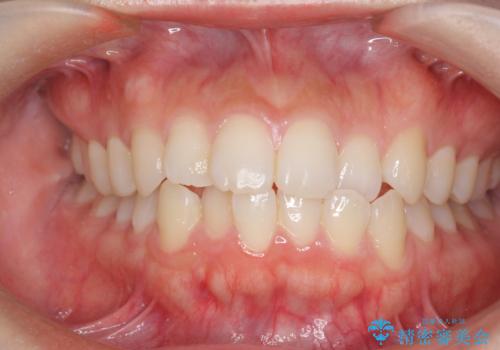

前歯のすれ違い インビザラインで行うマウスピース矯正

- 前歯のガタつき、でこぼこ、前後が逆になっている噛み合わせの改善を求めて来院されました。

治療の装置が目立たず歯ブラシのしやすいマウスピース矯正インビザラインでの治療を計画します。

20時間/日の装用時間をしっかりと守っていただき、きれいな歯並びを手に入れることができました。